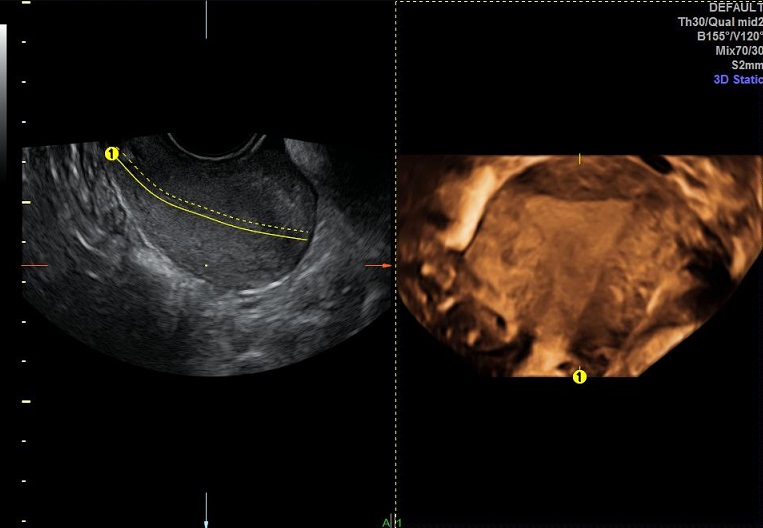

女性,30岁,继发性不孕2年,左侧输卵管宫外孕术后。常规二维超声子宫、卵巢及宫腔三维均未发现明显异常。宫腔置管后,宫腔水造影显示:宫腔稍见膨隆,内膜面光整,推注时有阻力。子宫输卵管实时三维超声造影显示:左侧输卵管未显示,右侧输卵管近端纤细,远端稍膨大,走行呈“S”行弯曲。诊断:左侧输卵管不通,右侧输卵管通而不畅。